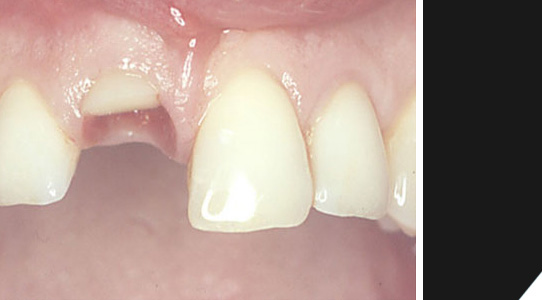

Hier sehen Sie das Beispiel eines Patienten mit Sportverletzung. Ein Rest des oberen rechten Schneidezahns ist noch vorhanden.

Der Restzahn wurde entfernt.